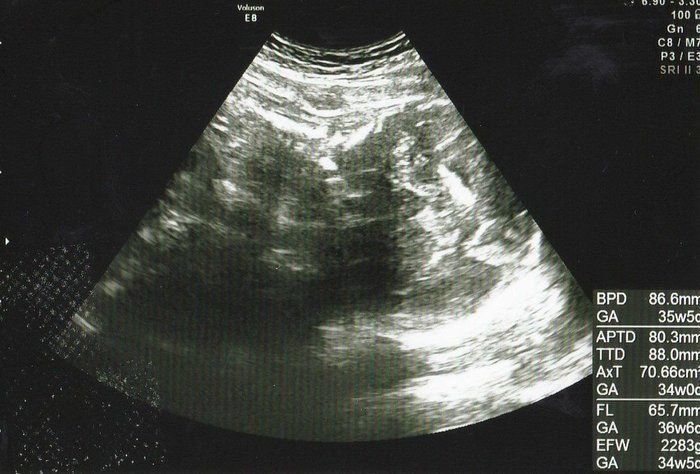

水野谷つむぎさんの妊娠32週目のエコー写真 赤ちゃんの推定体重2080g

この頃になると股関節痛が酷くなりました。少し歩いただけで、普通には歩けない状態になってしまい、道端でストレッチをしてしのいでいました。